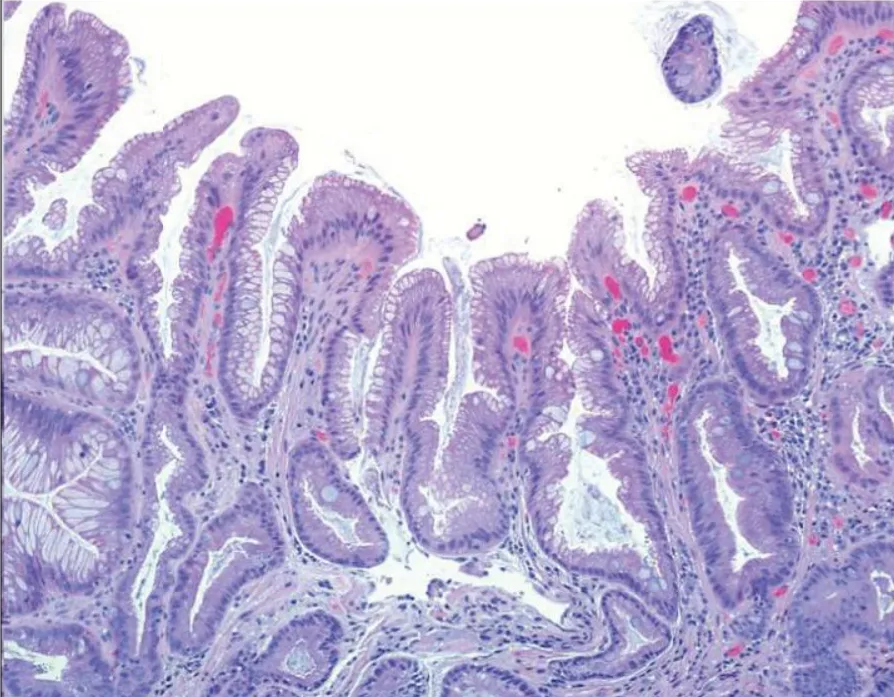

Метаплазия желудка — это патологический процесс, при котором нормальные клетки слизистой оболочки желудка заменяются клетками другого типа, более характерными для других отделов желудочно-кишечного тракта, таких как кишечник. Этот процесс считается предраковым состоянием и может служить этапом на пути к развитию злокачественных новообразований.

В норме слизистая оболочка желудка состоит из клеток, которые производят слизь, защищающую его от агрессивного действия желудочного сока. При метаплазии эти клетки заменяются на клетки, характерные для кишечника. Это нарушает процесс выработки желудочного сока и пищеварения, делает слизистую желудка более чувствительной к агрессивному воздействию соляной кислоты.

Кишечная метаплазия